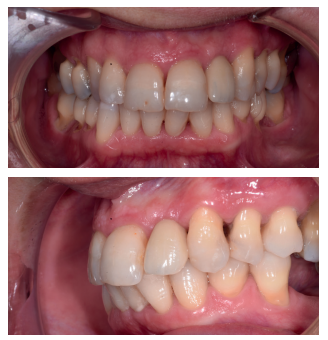

Tras 4 meses de la colocación del implante, habiendo cicatrizado ya el tejido blando después de la segunda fase (Figura 14) se copió el perfil de emergencia, para realizar la restauración fija implantosoportada, mediante una corona cemento-atornillada sobre un pilar de titanio, mostrando un buen aspecto clínico y radiográfico (Figura 15).

En cuanto al análisis de sonrisa, se consiguió también un buen aspecto estético, tal y como se observa en la Figura 16.

En la Figura 17 se puede observar el buen aspecto clínico de la restauración, 6 meses tras la intervención, y la buena aceptación de los tejidos blandos alrededor de la corona, dato que se verifica en la radiografía periapical paralelizada, observando neoformación ósea en las superficies mesial y distal del implante a los 6 meses, en comparación al momento de colocación de la corona (Figura 18).

de la corona en fotografía frontal (arriba) y lateral izquierda (abajo).